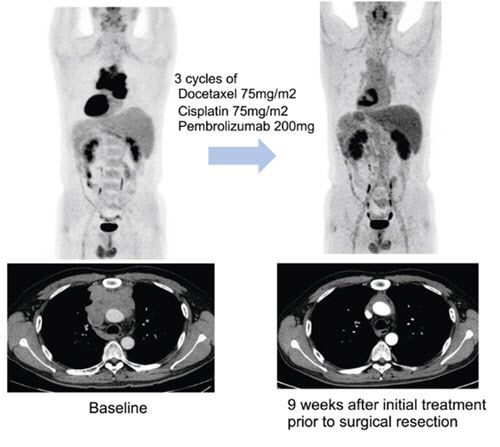

수술에 앞서 3주 간격으로 세 차례 항암화학요법에 면역항암제 펨브롤리주맙을 병용 투여한 결과병리학적으로 완전 관해를 보인 환자 예시. 연구팀은 이 환자가 3기 흉선암이었으나 현재 3년 이상 재발 없이 경과 관찰 중이라고 밝혔다. 연구팀은 “수술 시행한 환자 중 약 18%의 환자에서 완전 관해, 약 46%의 환자에서는 잔여 생존암이 10% 이하인 주요 부분 관해(major pathologic response)가 관찰됐다”고 밝혔다. |

연구팀은 이들 환자에게 3주 간격으로 세 번에 걸쳐 기존 항암화학요법에 펨브롤리주맙을 병용 투여한 다음 수술 가능 여부를 평가했다. 수술 후에는 최대 32주간 펨브롤리주맙 유지하는 한편, 일부는 항암방사선치료를 더하는 식으로 치료가 진행됐다.